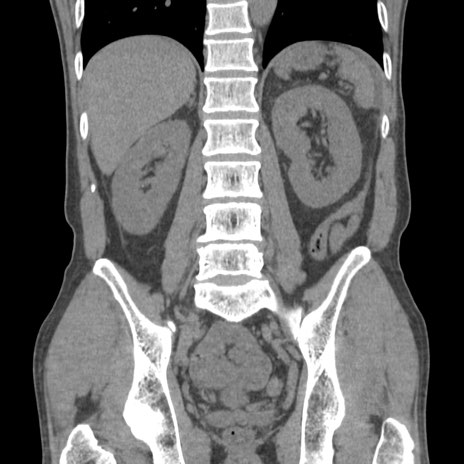

症例56 CT(冠状断像)

脂肪ウインドウ